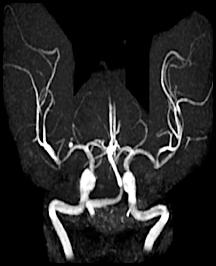

Cerebral hemorrhages are caused by the rupture of a weakened cerebral artery. Several things can undermine cerebral arteries including hypertension (classically occurring in the basal ganglia), atherosclerotic plaque, or aneurysms (such as the saccular or "berry" aneurysm visible in the angiogram to the left). Berry aneurysms usually occur near the circle of Willis. The resulting hemorrhage can occur either within the cerebral parenchyma or the subarachnoid space and can result in cerebral compression from a "mass action" effect.

Here are 3 angiograms. Each case represents either a thrombotic, hypoperfusion, and hemorrhagic stroke. Which is which?